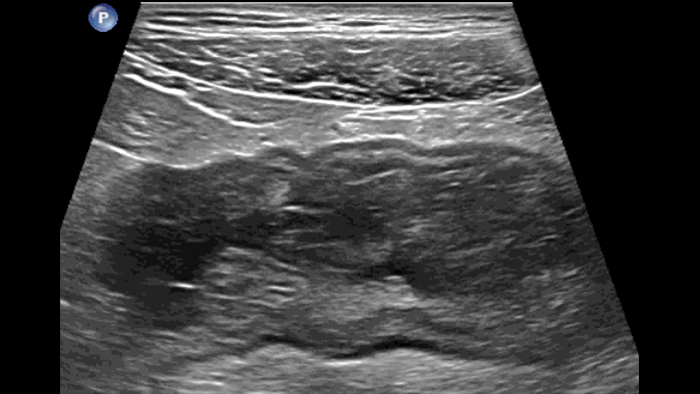

Dans le cas de la rectocolite hémorragique, en présence d’une forme grave et aiguë, la paroi est parfois plus épaisse. Ici, l’épaisseur des couches sous-muqueuse et muqueuse est augmentée en raison d’un œdème, tandis que la couche musculaire reste normale. En cas de forme chronique tardive, des pseudopolypes sont visibles à l’intérieur du lumen, ce qui n’a jamais été décrit à ma connaissance.

Severe acute form thick submucosal edema